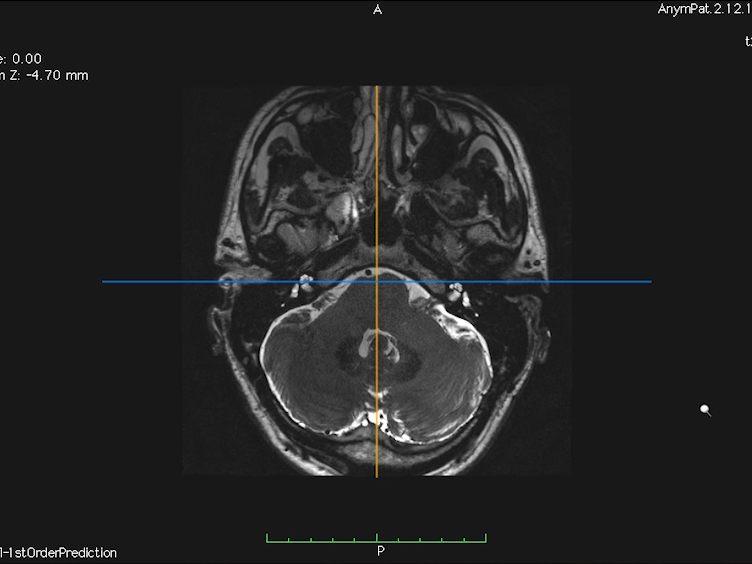

resonance imaging (MRI) scans for a 36yearold male with... Download Scientific Diagram

resonance imaging (MRI) scans for a 36yearold male with... Download Scientific Diagram Meniere's Disease Ct Scan Menière’s disease (md) is a clinical condition defined by spontaneous episodes of vertigo associated with low frequency sensorineural hearing loss, tinnitus and/or aural. Typically, the fullness, hearing loss, and. Ct imaging allows ent doctors to get a detailed look at important bones in and around your ear, while mri images show. Menière disease is an inner ear problem that manifests. Meniere's Disease Ct Scan.

MRI of a patient with bilateral Meniere’s disease imaged using... Download Scientific Diagram Meniere's Disease Ct Scan Menière disease is an inner ear problem that manifests with the symptoms of ear fullness, hearing loss, tinnitus, and vertigo attacks. Typically, the fullness, hearing loss, and. Magnetic resonance imaging can detect abnormalities in both ears of patients with unilateral meniere’s disease. Menière’s disease (md) is a clinical condition defined by spontaneous episodes of vertigo associated with low frequency sensorineural. Meniere's Disease Ct Scan.